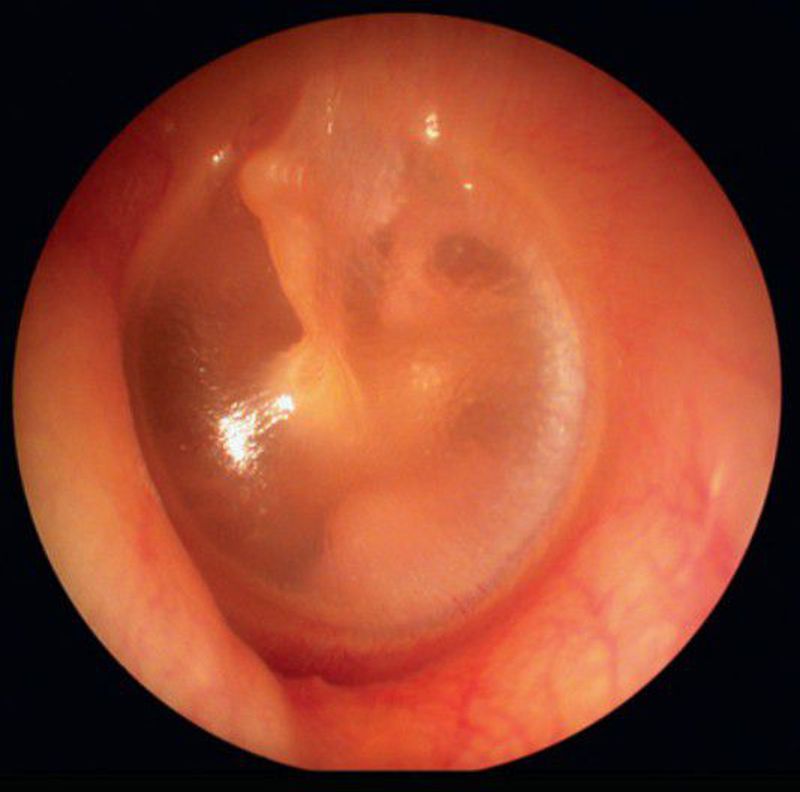

Its the attachment of malleus(ear ossicle) in middle ear to the tympanic membrane.